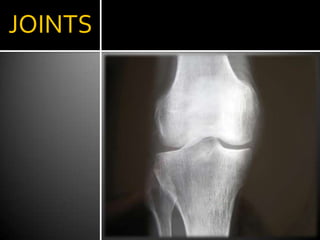

JOINTS

Arthritis of the joints – Synovitis.An inflammation of the synovial membrane that lines the joints and tendon sheaths.Joints become swollen, tender, and warm, and stiffness limits their movement.RA nearly always affects multiple joints.Common of joints affected are the small joints of the hands, feet, and cervical spine, as well as, larger joints such as the shoulders and knees.Synovitis can lead to tethering of tissue with loss of movement and erosion of the joint surface causing deformity and loss of function.Joints are often affected in a fairly symmetrical fashion, although this is not specific, and the initial presentation may be asymmetrical.